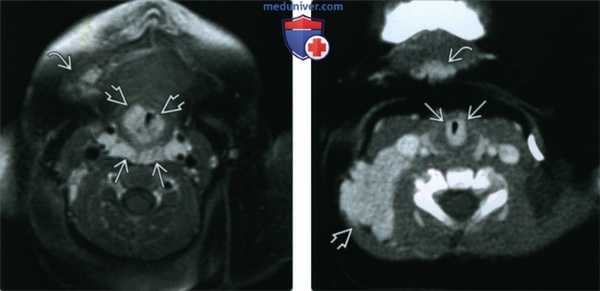

(Слева) МРТ Т1ВИ FS с КУ, аксиальная проекция. Ребенок с синдромом PHACES. Множественные накапливающие контраст гемангиомы в заглоточном пространстве В, вокруг подскладочного отдела трахеи и в правом подбородочном пространстве.

(Справа) КТ с КУ в аксиальной проекции, девочка 11 месяцев. Подскладочная гемангиома циркулярной формы с четкими контурами. Обратите внимание на гемангиомы заднего шейного пространства и подбородочной области, которые должны насторожить врача в отношении синдрома PHACES.

(Слева) При аксиальной МРТ Т1ВИ С+ FS у четырехмесячной девочки с синдромом PHACES в правом околоушном пространстве, задненижних отделах правой глазницы, правой щеке, носу, внутреннем слуховом канале и в области правого мостомозжечкового угла визуализируются множественные гемангиомы, накапливающие контраст. Обратите также внимание на гипоплазию правой гемисферы мозжечка.

(Справа) При аксиальной КТ с КУ у семимесячного ребенка с опухолью носа визуализируется объемное образование, интенсивно накапливающее контраст, и вызывающее окклюзию преддверия носа слева. Все характеристики и расположение этого образования типичны для МГ.

(Слева) При корональной МРТ Т1ВИ С+ FS у двухмесячного ребенка визуализируется крупная МГ, интенсивно накапливающая контраст, находящаяся как внутри, так и снаружи мышечной воронки глазницы; видно также другое объемное образование в области неба справа.

(Справа) При корональной МРТТ1ВИ С+ FS у этого же пациента шесть месяцев спустя после лечения пропранололом с целью предотвращения осложнений со стороны глазницы определяется существенный регресс объемных образований в глазнице и небе.

(Слева) При аксиальной КТ с КУ, выполненной девочке в возрасте одного года, определяется МГ очень большого размера, равномерно и интенсивно накапливающая контраст, практически полностью замещающая поверхностную и глубокую долю левой околоушной железы.

(Справа) При аксиальной МРТ Т1ВИ у этой же девочки восемь лет спустя определяется значительное уменьшение размеров гемангиомы и диффузное замещение ее жировой тканью. Обратите внимание на тонкую «полоску» ткани поверхностной доли околоушной железы.